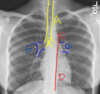

What structure is arrow #4 pointing to?

Pulmonary Arteries

What is structure E?

Pulmonary Hila